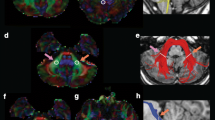

White matter morphology (FC) Fixel-wise comparisons showed significant negative associations between mean IES on the HRT and white matter morphology (logFC) in segments of the middle cerebellar peduncle (rho = − 0.88, pFWE < 0.05). Results are presented in Fig. 4. Additional effects trending towards significance (pFWE < 0.10) were observed in sections of the inferior cerebellar peduncles and the SLF I (see supplementary Figure S1).

Streamline segments showing a significant negative correlation (pFWE < 0.05) between mean IES and logFC within the middle cerebellar peduncle. To demonstrate the spatial extent of effects, results are presented using pFWE < 0.05 (yellow region) and pFWE < 0.10 (blue region). The scatterplot provides a visual representation of the association between mean logFC (averaged across the significant fixels form the CFE analysis) and mean IES

White matter morphology (FC) Significant negative correlations were observed between mean IES on the HRT and mean FC of the middle cerebellar peduncle (rho = − 0.62, p = 0.013, pFDR = 0.023), the left superior cerebellar peduncle (rho = − 0.63, p = 0.013, pFDR = 0.023) and the right superior cerebellar peduncle (rho = − 0.62, p = 0.014, pFDR = 0.023). We further observed an association for the left inferior cerebellar peduncle (rho = − 0.51, p = 0.052, pFDR = 0.065) that fell just short of statistical significance. No significant association was observed for the right ICP, and no significant associations were observed for any of the SLF segments. Significant associations are shown in Fig. 5.

Scatterplots showing significant associations between IES and mean FC values (residualised). Covariates include age and sex, and intracranial volume. The shaded area represents standard error. FC = fibre bundle cross-section; L = left; R = right; MCP = middle cerebellar peduncle; SCP = superior cerebellar peduncle